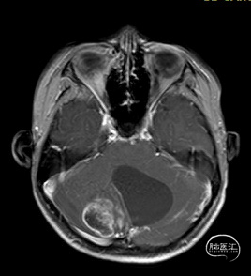

现病史:患者18个月前无明显诱因出现间断头痛,休息后可缓解,开始未予重视,未行特殊治疗。1周前患者无明显诱因出现恶心、呕吐,就诊于当地医院,行颅脑MRI提示:小脑囊实性占位性病变,首先考虑毛细胞星型细胞瘤。现患者为求进一步治疗就诊于我院,门诊以“脑肿瘤”收入院。患者自发病以来神志清,精神可,饮食睡眠正常,二便如常,体重未见明显下降。

术前MRI